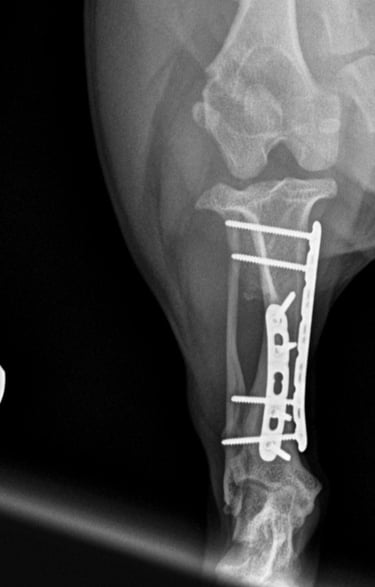

Tibia fracture - Mini Dachshund, 2y, female

This small and sweet 5.4 kg female patient sustained a lameness after playing in the garden allotment. Orthogonal radiographs revealed a surgical, long oblique spiral mid-diaphyseal fracture of the left tibia (Fig. 1 and 2).

Fig. 2